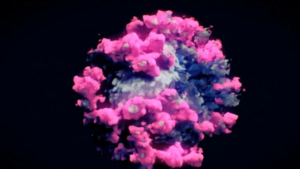

Yaklaşık 1.5 yıldır dünyanın başına bela olan corona virüsünün ilk kez fotoğrafı çekildi. Daha önceki versiyonları, hep gözlemlerin ışığı altında bilgisayarda oluşturulmuştu. Bu kez, çok farklı teknik kullanılarak, virüsün fotoğrafı çekildi ve aylarca süren çalışmayla da renklendirildi.

ÜÇ FARKLI TEKNİK KULLANILDI

Yeni tür corona virüsünü (Sars Cov-2) görüntülemek için Avusturya’da Nanografik isimli bir kuruluş çalışma yaptı ve Cryo-EM Tomografi ve 3D sistemi kullanıldı.

Ardından Viyana Teknik Üniversitesi’nde aylarca süren çalışma sonucunda, virüsün bir bölümü kirli mavi, bir bölümü pembe çıkıntılı yüzeyleriyle tüm gerçek şekli ortaya çıkarıldı. Yeni teknoloji ile fotoğraflanan, tüm ayrıntılarıyla ortaya çıkarılan virüs artık biyolojik mikroskoplarla daha detaylı olarak incelenebilecek.